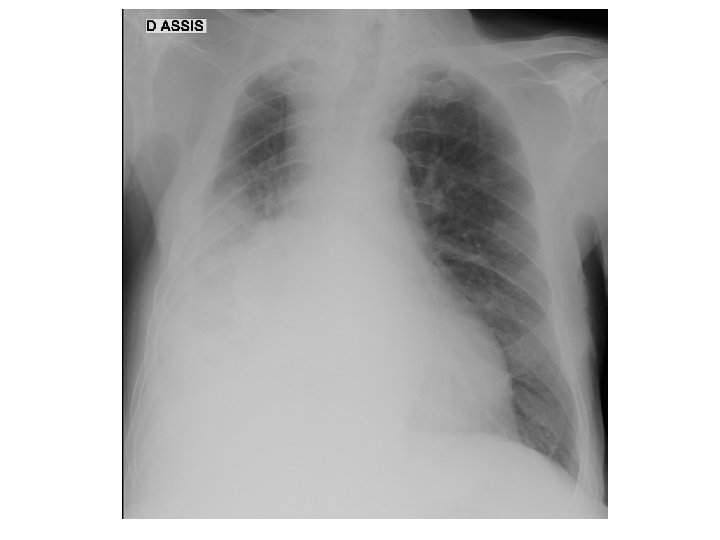

Hugues M… - 15/10/38 • Antécédents – HTA traitée par CELIPROLOL, – sciatalgie, – tabagisme sevré, 10 PA sur 35 ans, alcool : 2 verres de vin/jour, – Dupuytren bilatéral opéré à droite (droitier), – Canal cervical étroit opéré il y a un an – ulcère gastro-duodénal perforé – hernie inguinale bilatérale • Anamnèse – asthénie intense, anorexie, amaigrissement 2 kg – Anémie 8, 4 g/dl, VGM 87

Hugues M… - 15/10/38 • Examen clinique normal – Poids : 55 53 kg – Asthénie très inhabituelle – Pas de dyspnée • Examens biologiques – – – Na 131 mmol/l, K et créatinine normales Albumine 23 g/l Calcémie 2, 16 mmol/l CRP 124 mmol/l Cholestase minime isolée

Hugues M… - 15/10/38 • Diagnostic : cancer bronchique à petites cellules avec métastases hépatiques multiples